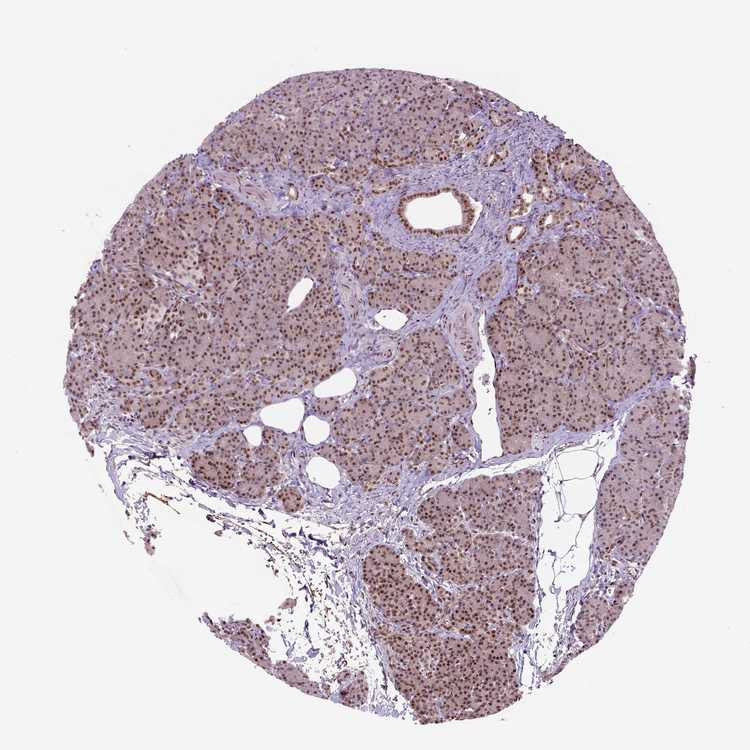

PANCREAS - Antibody stainingi

Antibody staining in the annotated cell types in the current human tissue is reported as not detected, low, medium, or high, based on conventional immunohistochemistry profiling in selected tissues. This score is based on the combination of the staining intensity and fraction of stained cells.

Each image is clickable and will lead to virtual microscopy that enables deeper exploration of all samples and also displays staining intensity scores, fraction scores and subcellular localization as well as patient and tissue information for each sample.

Antibody HPA069497Antibody CAB002786Antibody CAB069881

Exocrine glandular cells Not detectedHighMedium

Pancreatic endocrine cells Not detectedMediumMedium